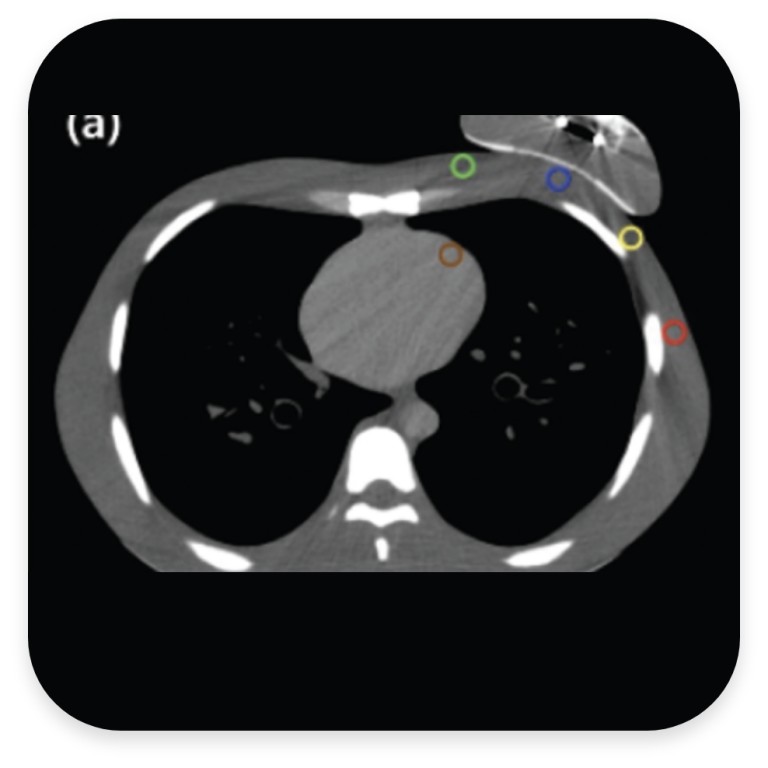

CT images with Motiva Flora® SmoothSilk® Tissue Expanded and a Traditional Magnet Port

An example of the CT image (a) RFID port, (b) metallic port analysis using five reference points; a: central chest wall (blue), b: medial chest wall (green), c: lateral chest wall (yellow), d: axilla (red) and e: left anterior descending artery (brown). Extracted from Hwang et al. 2021